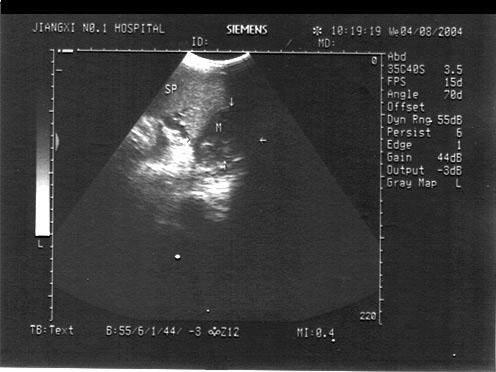

问题 男,有结肠癌病史。结合超声声像图,诊断为?(?)

选项 A.脾转移性肿瘤 B.脾梗死 C.脾血肿 D.脾脓肿 E.脾血管瘤

答案 A